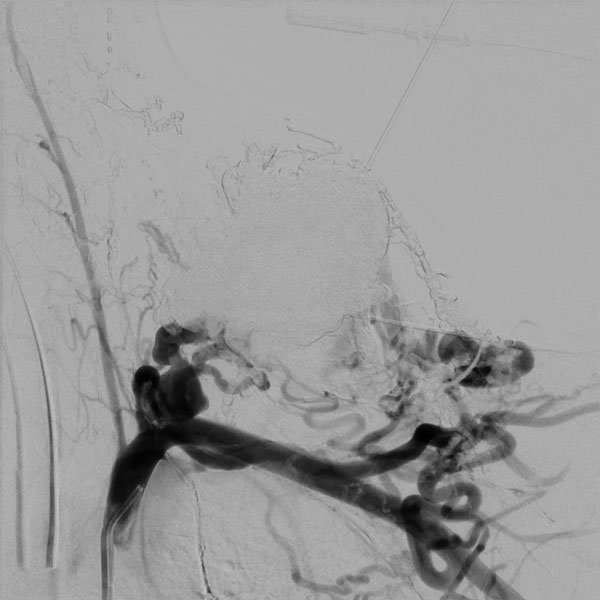

In der digitalen Subtraktionsangiographie (DSA) nach Injektion in die linke A. carotis communis stellen sich multiple, kaum zählbare zuführende arterielle Feeder dar, die den Nidus der arteriovenösen Malformation speisen. Sofortiger und direkter venöser Abstrom aus der Läsion.

Digitale Subtraktionsangiographie (DSA) nach Injektion in die linke A. subklavia. Es stellen sich ebenfalls unzählige zuführende arterielle Feeder dar, direkt aus der A. subklavia, aber auch multiple Zuflüsse direkt aus der linken A. vertebralis. Aufgrund der multiplen, feinen, kaum einzeln identifizierbaren arteriellen Zuflüsse ist eine rein transarterielle Embolisation technisch nicht möglich und auch nicht zielführend.